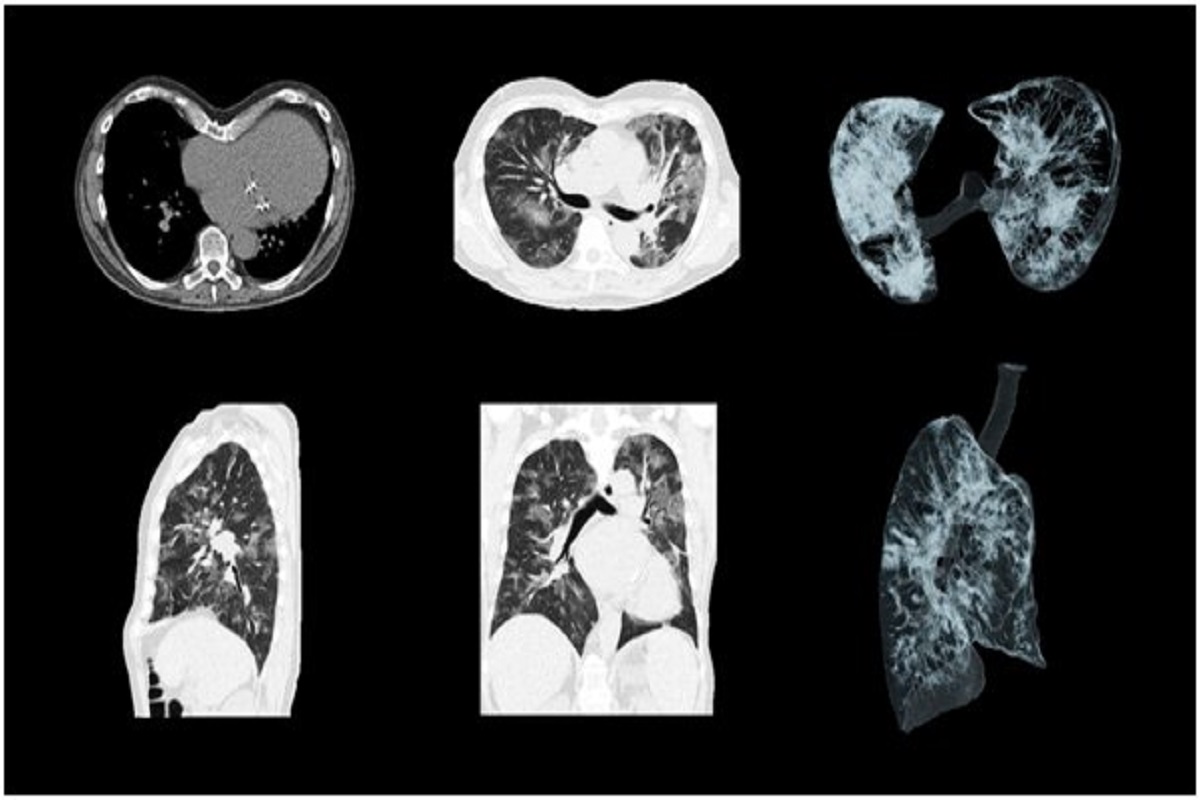

Role of CT Chest and Teleradiology for 30 Minute Report in Current Role Of Tele Radiology At its core, telemedicine leverages digital technologies to facilitate remote consultation, diagnosis, and treatment planning. They play a crucial role in patient care by delivering. Teleradiology is the electronic transmission of radiological images from one location to another with the main purpose of. Teleradiologists, like those partnered with teleconsult, interpret medical images remotely. The practice of teleradiology is one of. Role Of Tele Radiology.